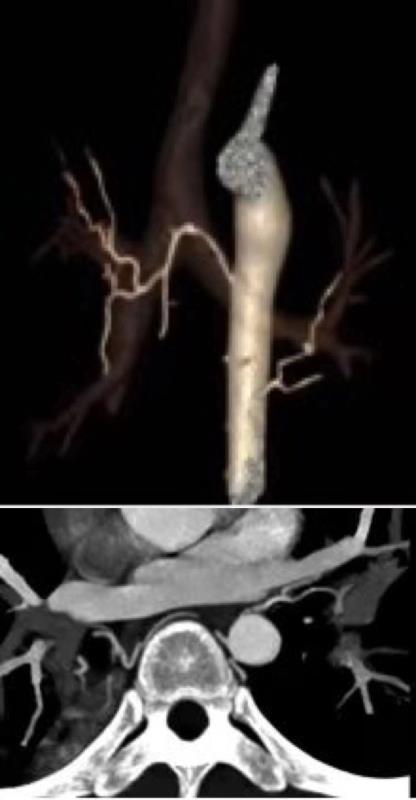

随着CT技术的发展,CT血管成像(CTA)的应用越来越广泛,本课题主要探讨支气管动脉CTA检查影响其阳性显示的主要因素以及本地区普通人群BA分布图。支气管动脉(BA)是肺支架组织的营养血管,其多发自胸主动脉,走行于纵膈间隙,攀附于支气管壁经过肺门进入肺组织,形成毛细血管网并营养周围组织。BA本身管径细小(1-2mm),走行迂曲,行程不定;起源、开口位置及数目变异大,若能在实施介入治疗前对BA的分布、形态及与疾病的关系有一全面了解,将对介入治疗提供重要帮助。

研究认为,支气管动脉作为肺部介入手术的主要靶血管,在实施介入手术前,对有肺部基础疾病的患者行支气管动脉CTA检查,支气管动脉能都得到阳性显示,同时能提供一个非侵入性评价支气管动脉及其肺部病变的有效方法。

因为支气管动脉起源变异明显,该科研课题的应用,术前能把支气管动脉的起源及走行显示的更清楚,更有利于提高手术成功率,减少术后复发的机会,降低医疗风险,是一种安全有效、经济实用的方法,该技术值得临床推广应用!